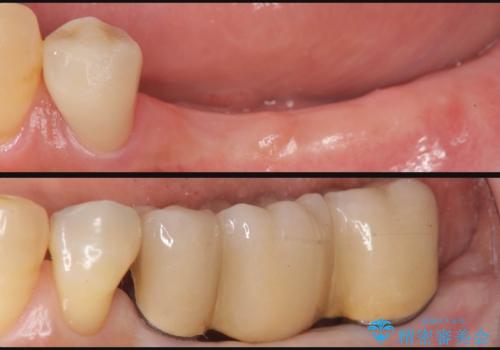

咬合機能を回復し、満足して食事を行えるようインプラント治療を計画します。

- 80万円(インプラント×2・アバットメント×2・ジルコニアクラウン×3)費用は治療当時の料金となります